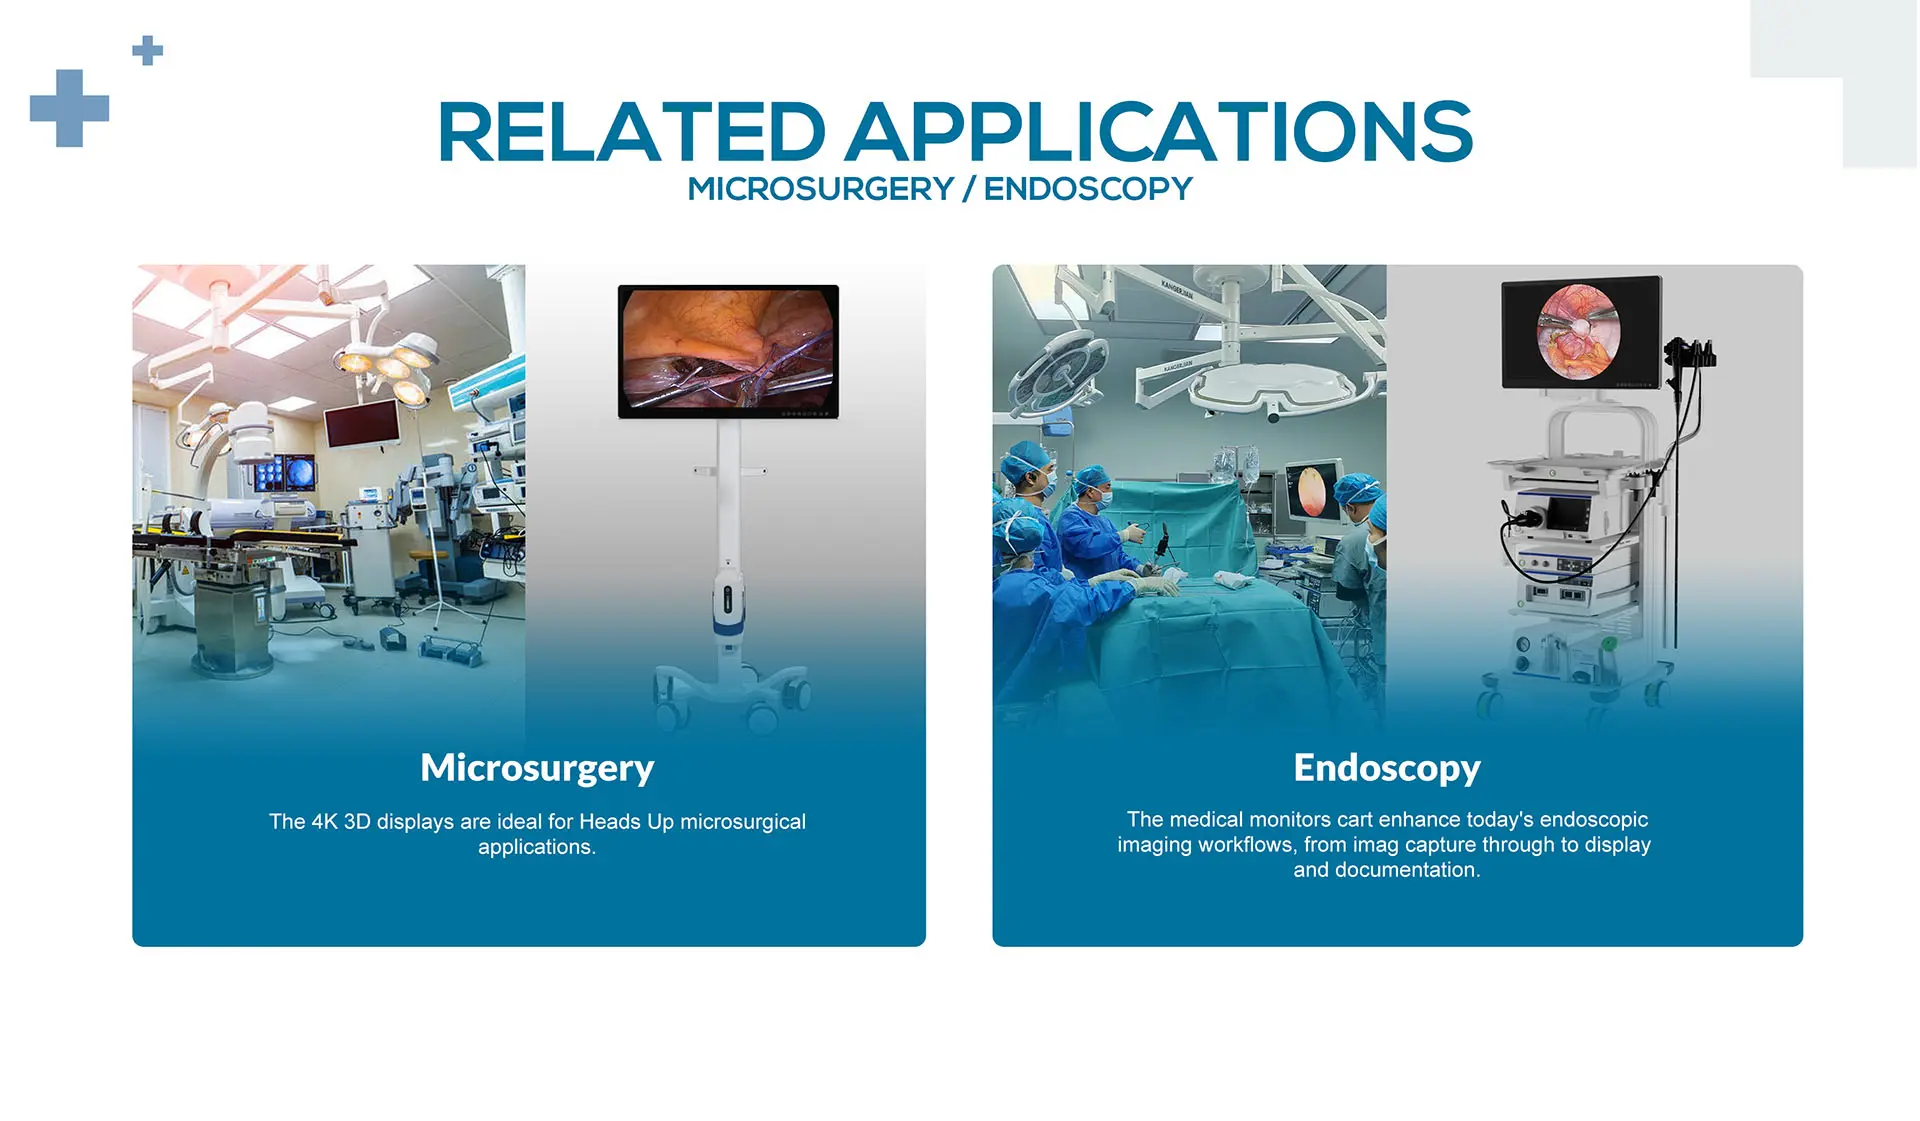

MD31 is a 31.5" 4K surgical monitor for endoscopy and surgery, with accurate color reproduction, clear contrast and vivid video images, providing surgeons and operating staff with real-time, accurate color images. Antibacterial housing and optical bonding technology are easy to clean and disinfect. A variety of video input andoutput interfaces can accommodate video signals from various medical imaging sources to meet the requirements of various applications in the operating room.